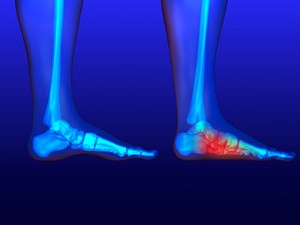

Common Types of Fractures on the Outside of the Foot

The fifth metatarsal bone—the long bone connected to the little toe on the outside of the foot—is prone to breaks, with the two most common being Avulsion fractures and Jones fractures. Avulsion fractures usually occur from an injury that causes tendons or ligaments to pull a portion of the bone away from itself. A Jones fracture is less common, occurs either over time or suddenly, is harder to treat, and takes longer to heal due to less blood flow to the area. People suffering from either type of fifth metatarsal fracture can experience bruising or discomfort along the outside of the foot including tenderness, swelling, and pain. Some may even have difficulty walking. A podiatrist can properly diagnose the type of break and use several types of therapies and procedures to facilitate healing.